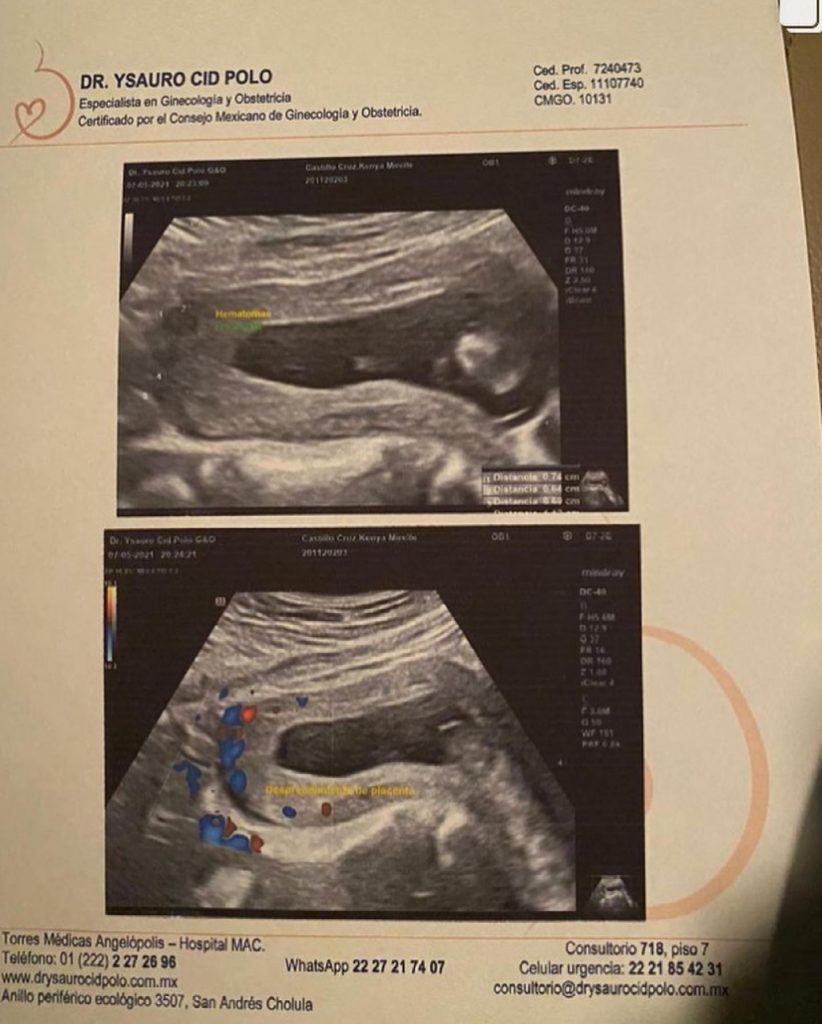

Puebla.- Kenya Mirelle Castillo Cruz tiene 10 semanas de embarazo. Ahora tiene hematomas, desprendimiento de placenta, esguince y el tabique desviado. El motivo. Su expareja la golpeó y pateó cuando estaba en estado de ebriedad.

Tengo amenaza de aborto, hematomas internos, desprendimiento de placenta, tabique desviado y esguince en cuello. Necesito ayuda de todas las personas para que esto no se quede en un carpetazo más”.